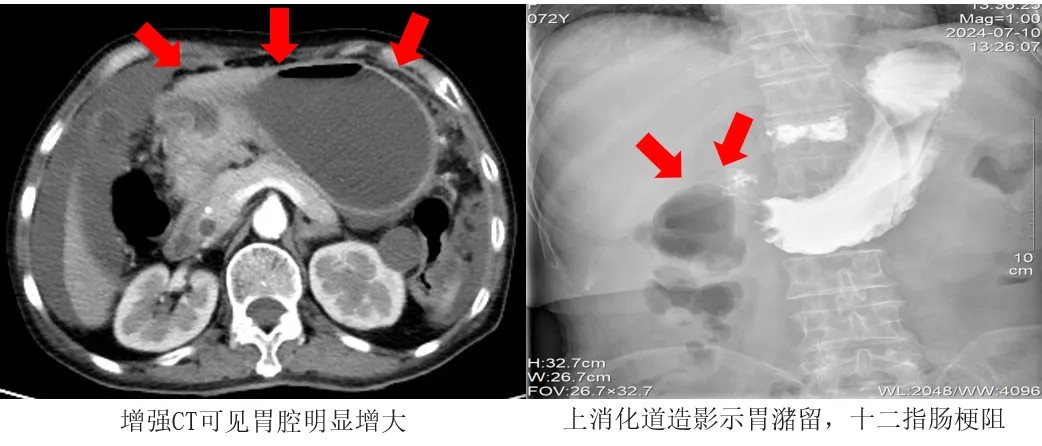

不久前,72歲的王阿姨罹患胃癌,發現時已為癌癥晚期,癌細胞已擴散至腹腔,無法行外科手術根治。但腫大的腫瘤組織嚴重壓迫胃的幽門及十二指腸部分,導致消化道梗阻。

來院就診時,王阿姨已有半個月無法正常進食,嚴重消瘦,存在嚴重的營養不良、低蛋白血癥、低鉀血癥和貧血,每日僅靠輸注營養液維持。俗話說“民以食為天”,無法進食讓王阿姨痛苦萬分,甚至一度失去了繼續治療的信心。家人心急如焚,“能吃飯”成了患者和家屬最大的心愿。

考慮到王阿姨高齡、手術耐受力差,介入科團隊決定為其行十二指腸支架植入術治療,用支架撐開腸道,讓狹窄部位恢復通暢。

術前,醫療團隊通過鼻腔將胃腸減壓管插入脹大的胃腔,通過負壓球吸引出了已積蓄多日的數千毫升的胃內液體,使胃的體積恢復正常。

術中,醫生拔除胃腸減壓管,隨后通過王阿姨口腔,利用導管與導絲配合,精準進行了幽門插管操作,并成功穿越了狹窄區域。緊接著,他們沿著導絲順利放置了一枚十二指腸支架,且在透視下確認了支架的位置完全符合要求。